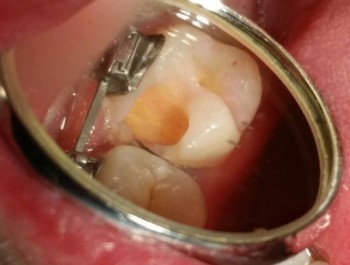

Писарская Елена Николаевна: портфолио (2)